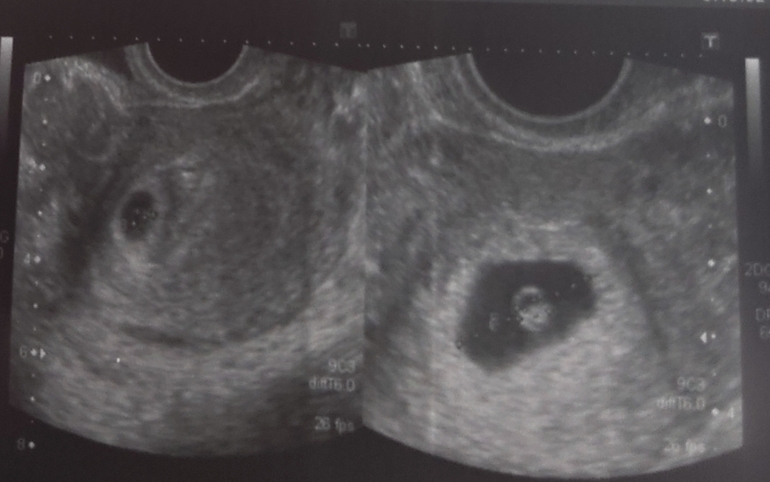

сделала узи на нормальном аппарате креветочки мои сладенькиеееееееее!

пя отличаются по размеру, но так было изначально 4.3 и до 5мм, через неделю 10 и 12 мм ктр тоже разный 2.9 и 4.5 мм

увидела как пульсируют сердечки моих крошечек! 91 и 95 чсс читала, что при двойне это нормальная чсс